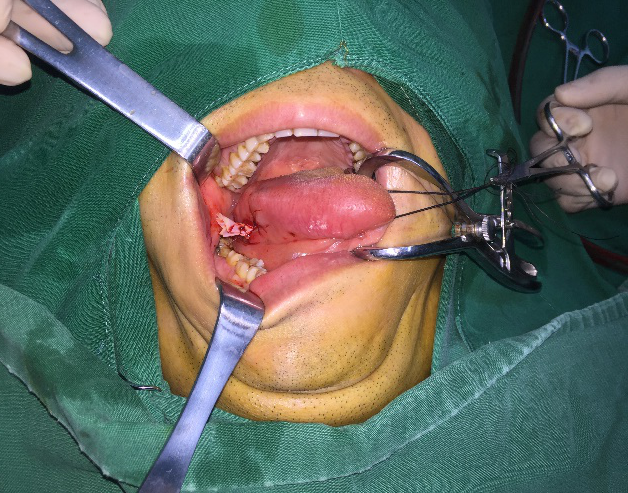

所以在这个情况下进行操作,手术就非常关键。术中我们是如何做的呢?首先是打开脓腔,沿着脓腔纵向切开舌侧缘,用小的镊子一点点地去探及这个异物,找到了之后,要小心翼翼地拔出,完整地把鱼刺取出来,拔出来以后还要观察一下拔出的鱼刺,查看是否完整,尖部是否有断裂。

图一:打开脓腔

图二:取出鱼刺

像这样把鱼刺取出后,接下来还要再把脓腔和炎性肉芽搔刮干净,如果脓腔深还需要放置引流片。

图三:放引流片